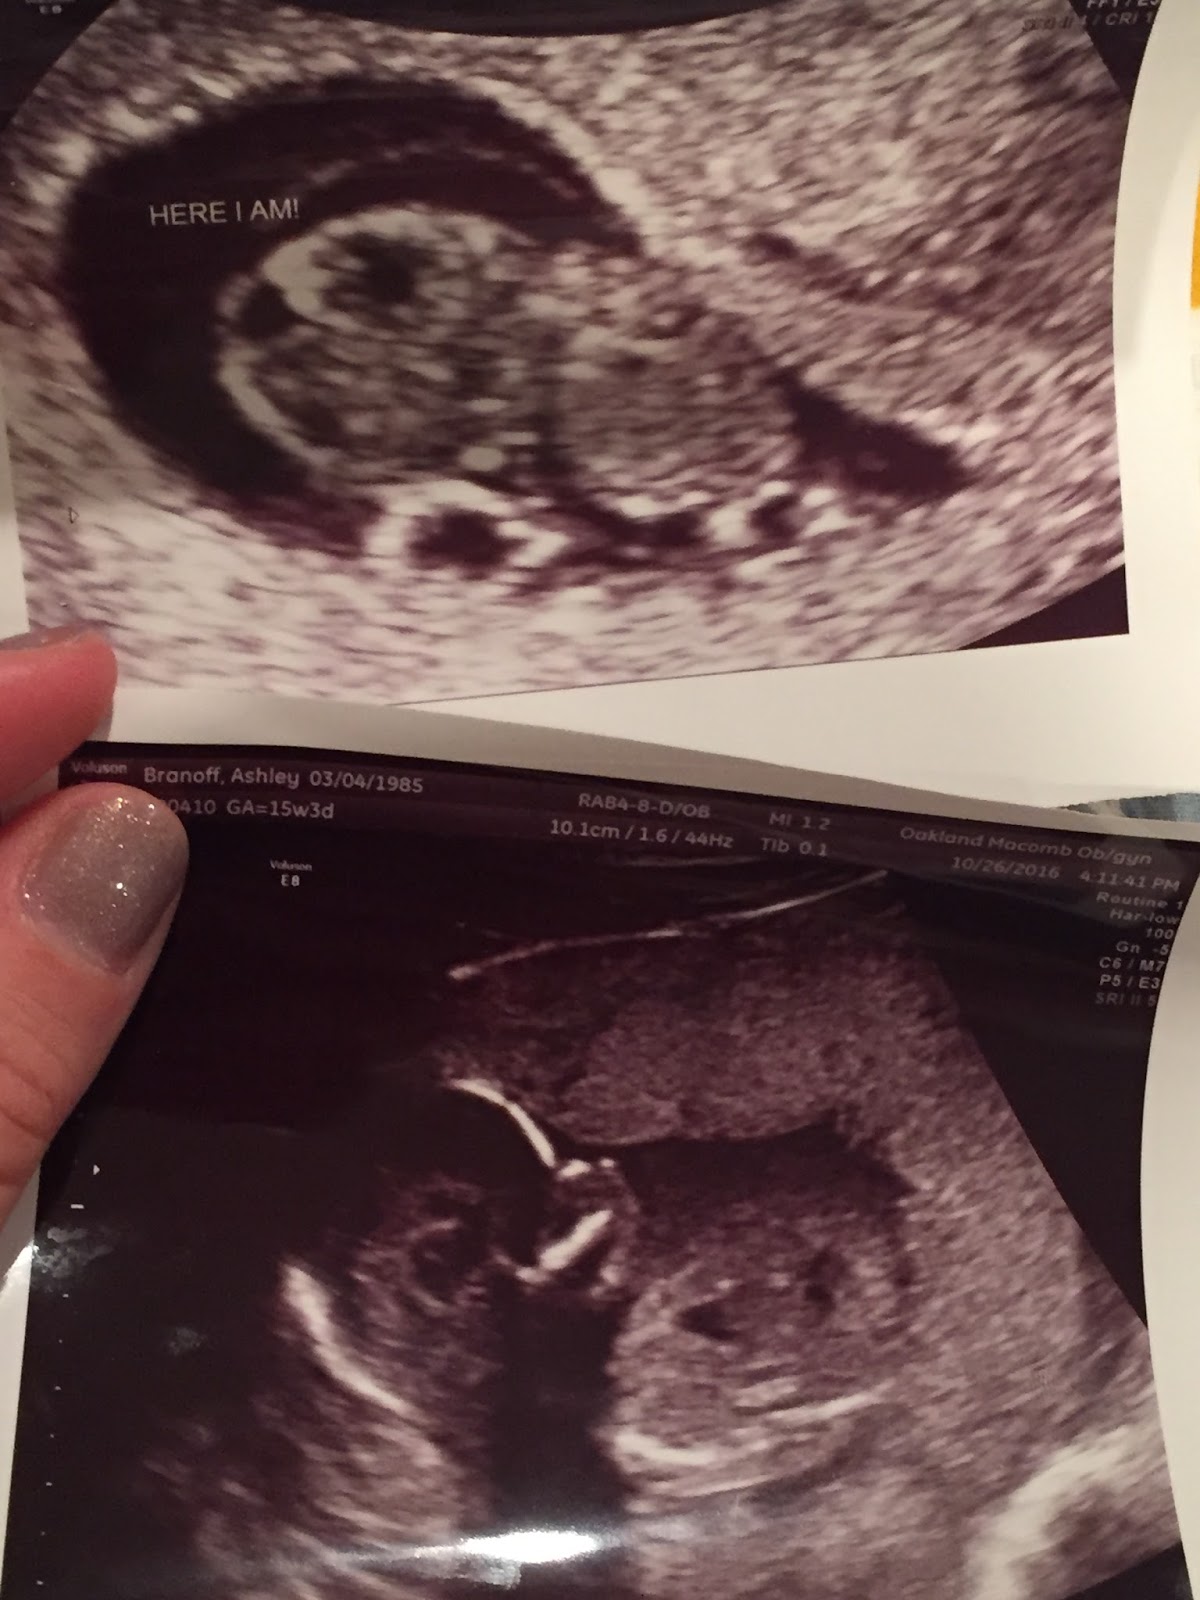

The first and last pictures I have of Baby Boy

As I look back through my box, the box they give you of mementoes of the child you lost so you don't leave the hospital with nothing, I am overwhelmed with emotions. It contains forget-me-nots, a knitted blanket, and a necklace from strangers who put together gifts for people in my situation so it doesn't hurt so badly. It contains a measuring tape marked with how long he was (7.5"), the blanket I held him in, still stained with blood, his ultrasound photos, and his tiny footprints the nurse did for me. It also contains letters from people I know well and those I don't know at all, expressing empathy, condolences and love. I also have necklace and bracelet that I wear, one stating "Brave" and the other of the April birthstone to remember him that are not in the box that have meant so much to me.